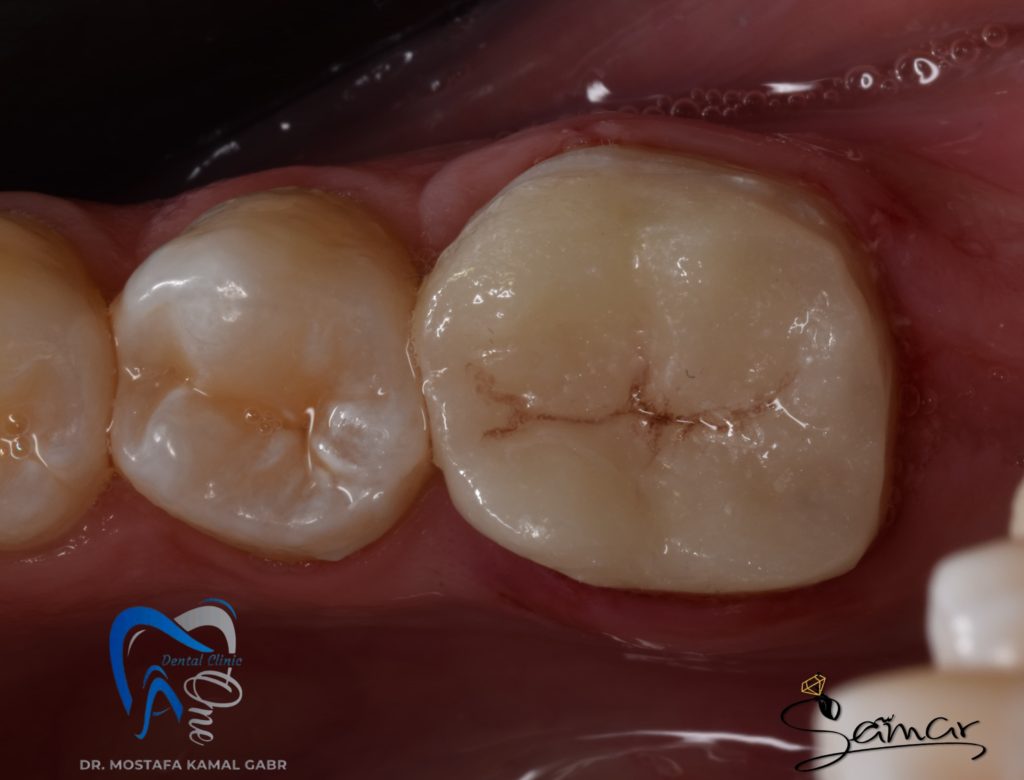

This was the initial situation before any tooth structure removal